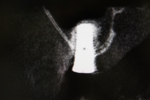

サイナスリフト(骨移植)併用インプラント埋入

ご覧の通り全く骨がないので骨を造りインプラントを埋入しました。

隣の歯も状態が良くなく予後が悪そうです。

抜歯後はインプラントをご希望でしたので、サービスで同部にも骨を移植しておきました。

これで次回オペ時の患者さんの移植のリスクが軽減しました。